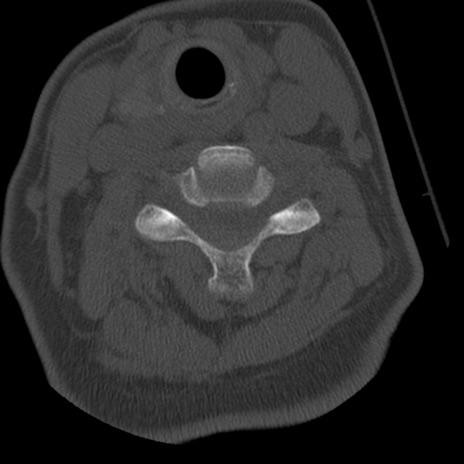

症例50 頚椎CT(横断像)

異常所見と診断は?

頚椎CT